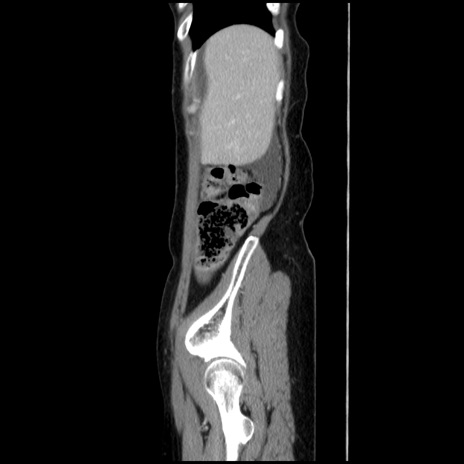

症例32(矢状断像)

【症例】40歳代 女性

【主訴】上腹部痛、嘔気・嘔吐

【現病歴】約9時間前頃から急に上腹部痛、嘔気、嘔吐が出現。改善しないため救急要請。

【既往歴】子宮頚癌(広汎子宮全摘術、放射線療法)、腸閉塞

【身体所見】腹部:平坦、軟、腸雑音亢進、上腹部を中心に腹部全体に圧痛あり。

【データ】WBC 8400、CRP 0.03